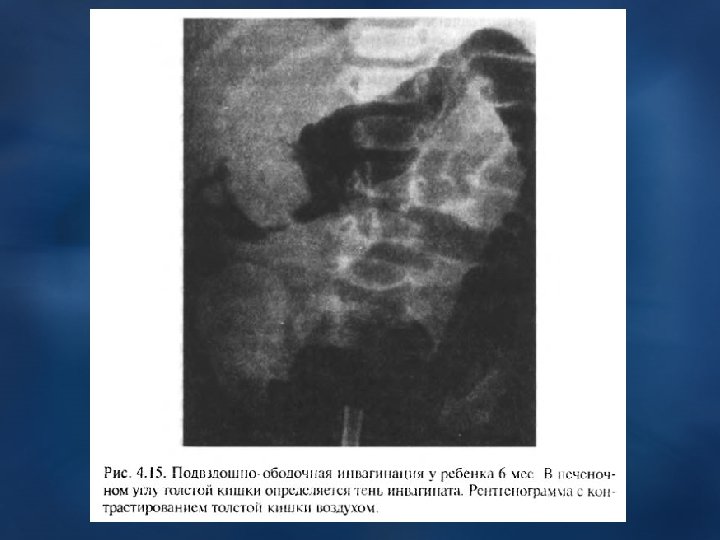

ИНВАГИНАЦИЯ КИШЕЧНИКА Наиболее часто встречается у детей, особенно 1 -го года жизни (70 %), встречается в 2 раза чаще у мальчиков чем у девочек. Характерно: острое внезапное начало (во время сна или кормления), ребенок вскрикивает от сильной боли в животе, начинает беспокоиться, затем плакать, кричать, отказываться от груди, “сучит ножками”. Боли приступообразные со «светлым» промежутком (на 5 -10 мин). После 1 -го приступа болей может начаться рвота, а через несколько часов – задержка стула и газов. Прожилки крови в стуле или чистая кровь важный, но поздний симптом Через 8– 12 часов наступает интоксикация организма, обезвоживание с нормальной или t 0 тела. Может наступить шокоподобное состояние. тела Осмотр: язык сухой, обложен, Ps частый, слабого наполнения, дыхание поверхностное и шумное. В начале живот мягкий, доступен глубокой пальпации во всех и шумное отделах. Справа от пупка, чаще в области правого подреберья, можно обнаружить отделах опухолевидное образование мягкоэластической консистенции, малоболезненное при пальпации. В поздней стадии болезни – живот вздут, напряженный, резко болезненный при пальпации во всех отделах. Обзорная рентгенография: затемнение в правой полости живота; : Ирригоскопия с бариевой кашей / воздухом: видны внедрение одной части кишки в : другую, подвздошной в ободочную, инвагинация в толстом кишечнике. На месте инвагината барий встречает препятствие, образует “чаши”, полукруги, “трезубцы”. Лечение: в первые 12 ч. неоперативное (баллон Ричардсона). После – резекция участка кишки.